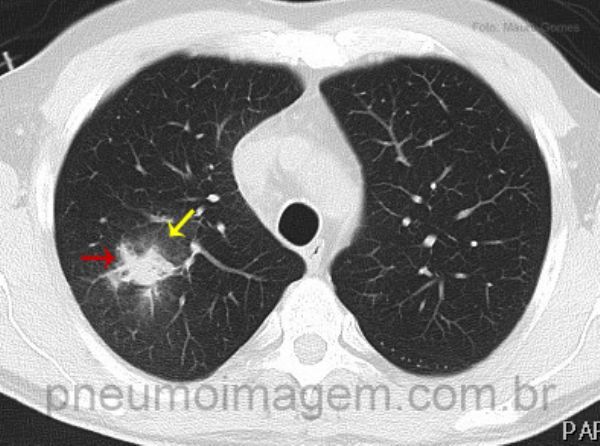

ASPERGILOSE INVASIVA - 2

A Aspergilose Invasiva (AI) é rara e ocorre principalmente em hospedeiros imunocomprometidos. Neutropenia e uso prolongado de glicocorticoides são os fatores predisponentes mais comuns. AI leva ao óbito em 70-90 nos imun...